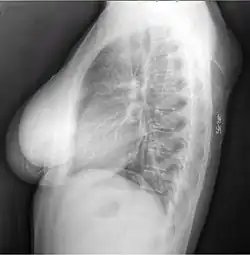

Diagnosis

A physical exam is typically the easiest way to diagnose it. Rarely, a tissue biopsy or imaging may be required. The imaging modality of choice is magnetic resonance imaging (MRI) because it has superior sensitivity of distinguishing it from liposarcoma as well as mapping the surrounding anatomy.[22]